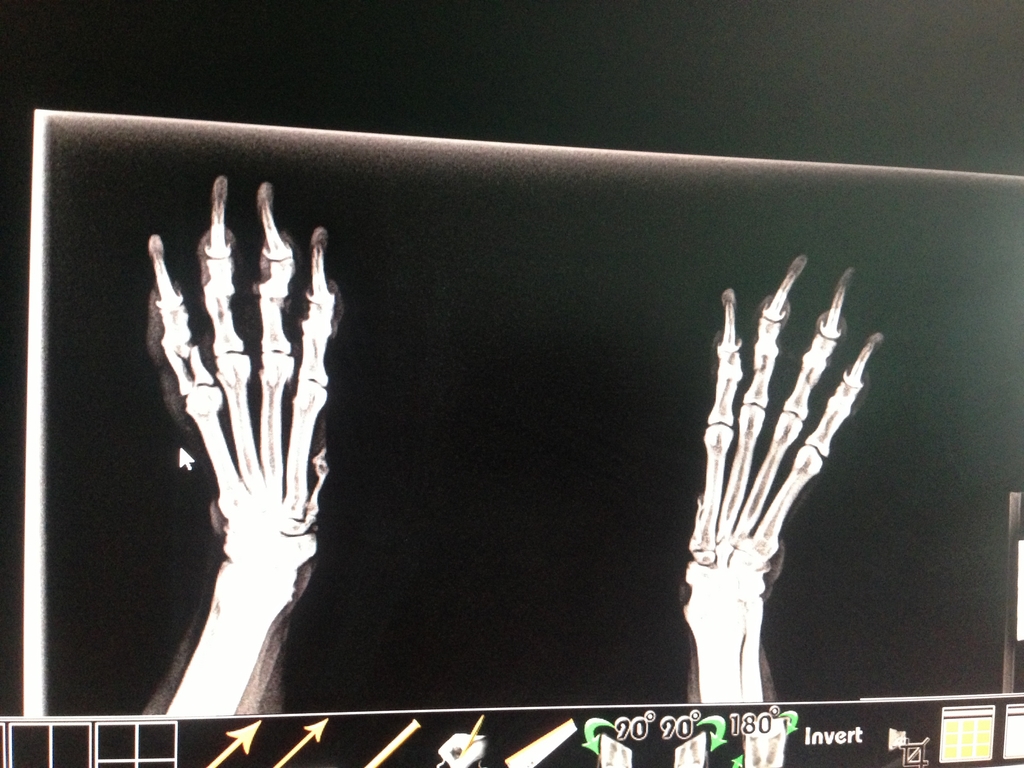

One X-Ray later…

(note the “two piece” bone in the left foot)